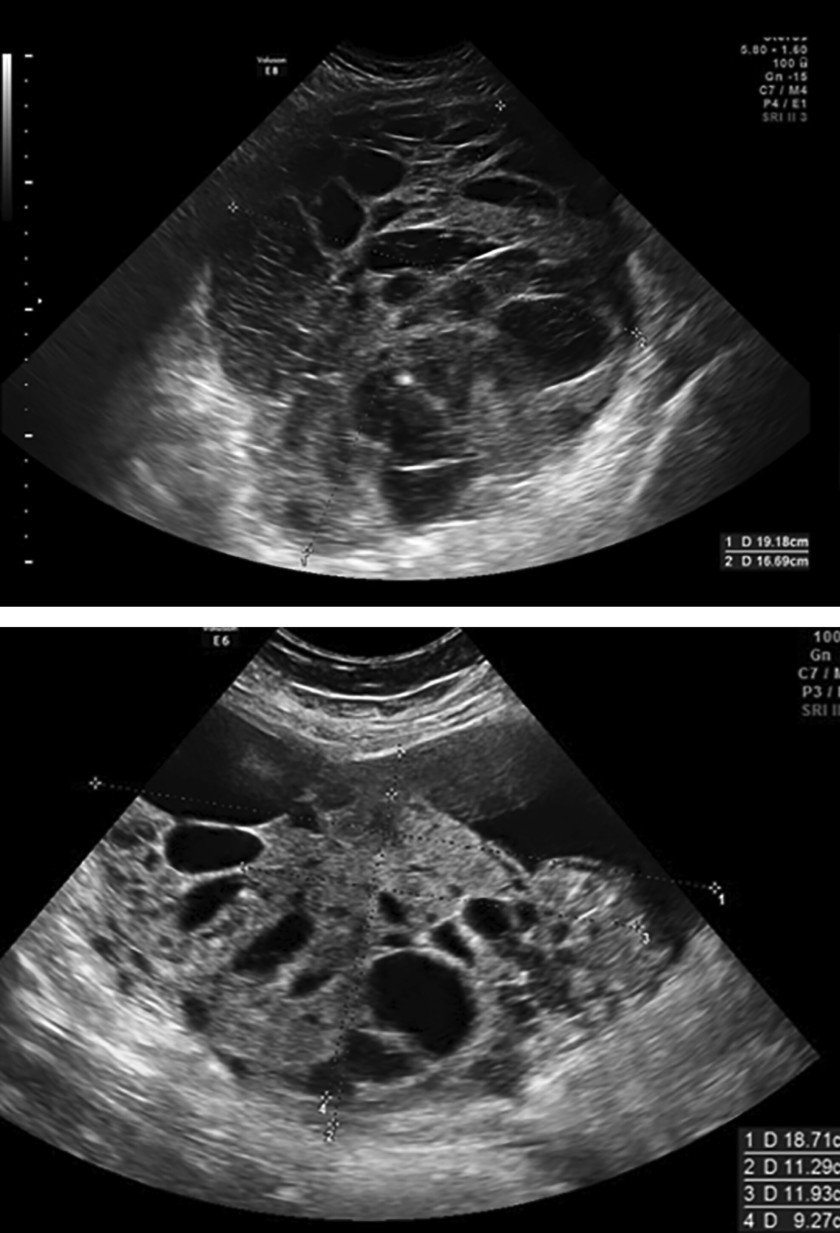

​De diagnose is een dooierzaktumor (Yolksac Tumor), een zeldzaam subtype binnen de kiemceltumoren. Om de zeldzaamheid in context te plaatsen: kiemceltumoren zijn goed voor slechts ongeveer 3% tot 5% van alle eierstoktumoren bij volwassen vrouwen.